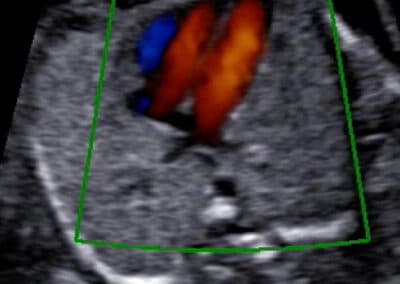

Srdíčko v při barevném Dopplerovském zobrazení

Srdíčko miminka vyšetříme nejprve v běžném šedobílém zobrazení, během kterého zkontrolujeme jeho polohu, velikost a stavbu. Navíc změříme velikosti cév odstupujících ze srdce. Potom pomocí Dopplerovského vyšetření zhodnotíme směry toku krve a změříme rychlosti průtoku krve srdečními oddíly.